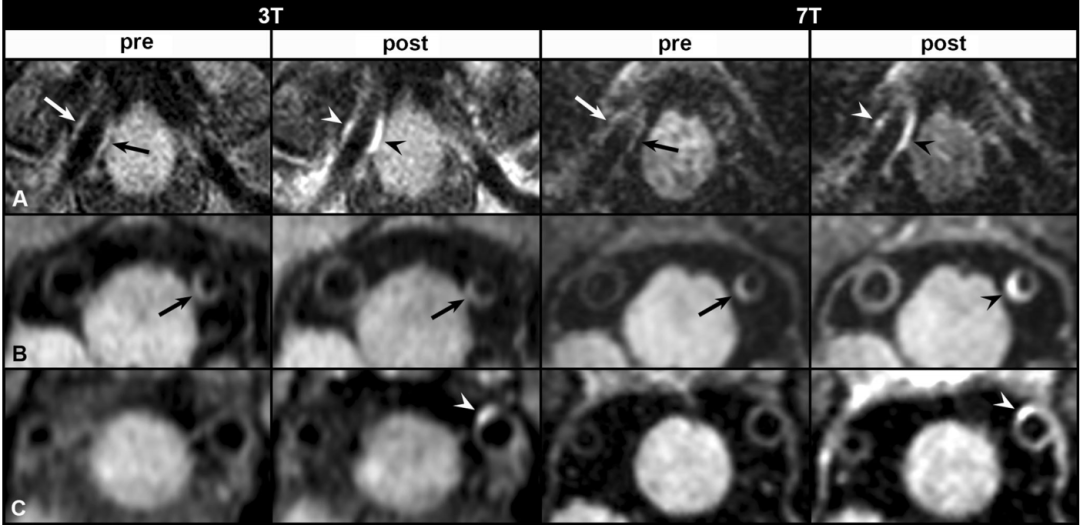

结果:与3-T相比,7-T MRI 图像血管壁能见度相等或明显更好。7-T更好的血管壁可视化能力在近端脑前循环近端和大脑后动脉处表现最为突出。在研究的老年无症状人群中,3-T MRI鉴定出48个血管壁病变,其中7个显示增强, 7-T MRI 发现了79个病变,其中29个显示增强。7-T识别出的所有病变,近一半在3-T上无法识别。

3-T和7-T图像识别出的病变数量、位置和增强